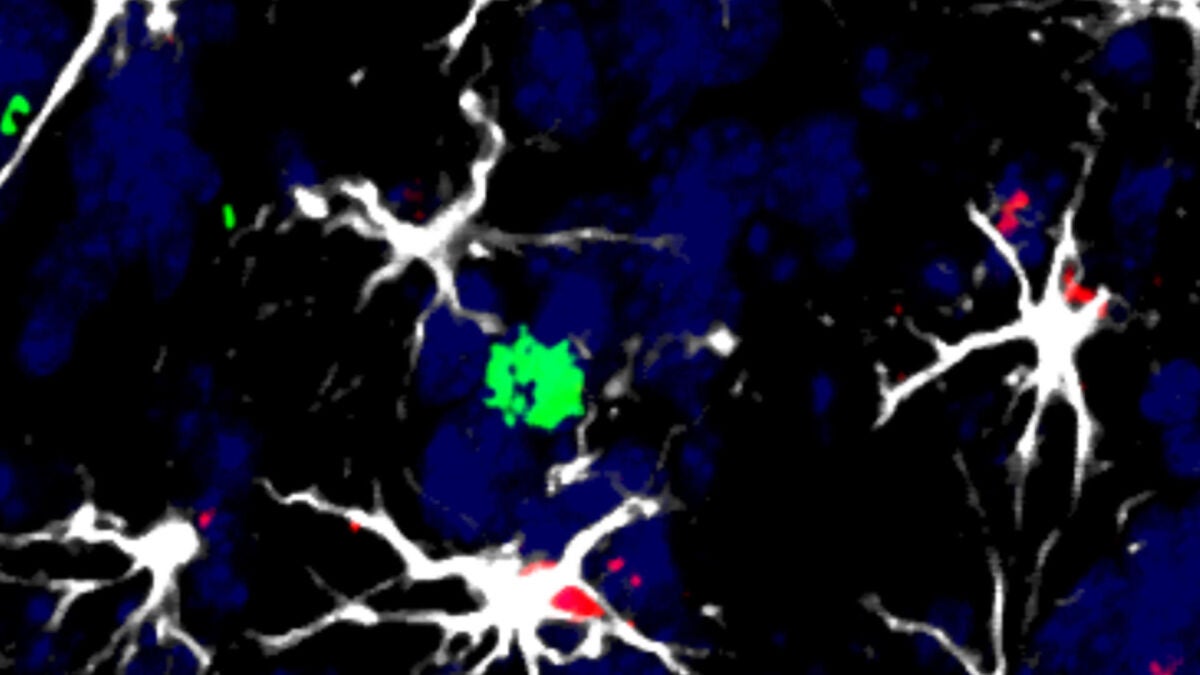

Concretamente, han identificado unas células cerebrales llamadas astrocitos que dificultan el trabajo del sistema inmunológico y le impiden matar las células tumorales.

"Los astrocitos pro-tumorales producen una molécula llamada TIMP1 que interviene en la inhabilitación de las células defensivas que deberían acabar con las células cancerígenas", señala otra de las autoras, la investigadora del CNIO, Neibla Priego.

"Hasta ahora no se había considerado a los astrocitos como inmunomoduladores, ni en estudios generales ni, desde luego, en relación con los tumores cerebrales. Nuestra investigación no es solo innovadora desde el punto de vista clínico, también lo es, y mucho, para el avance del conocimiento científico", subraya Valiente.